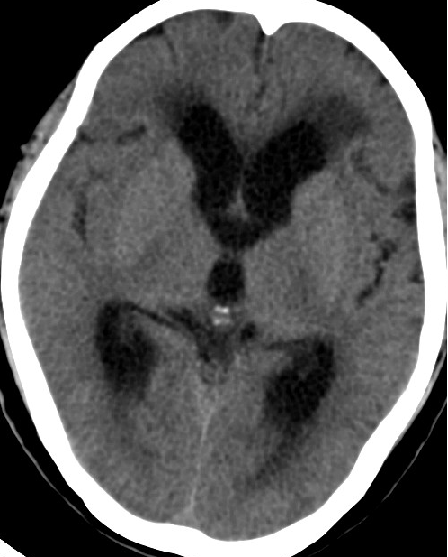

2014-10-17 CT

仍时有前额部疼痛,程度轻,调压190—200